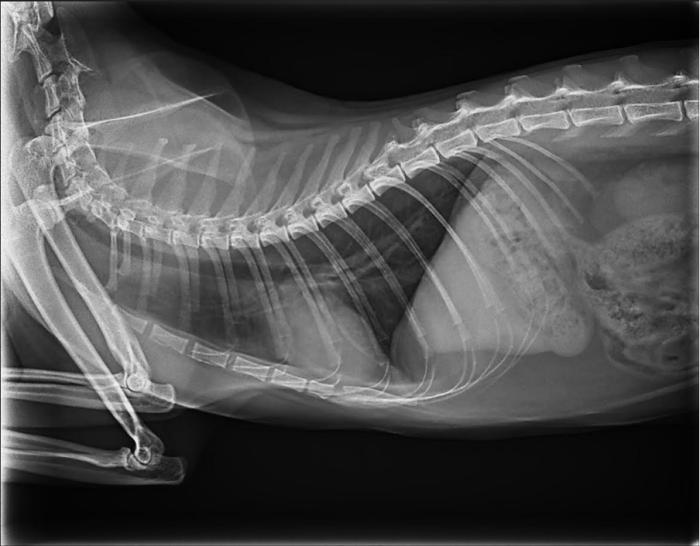

Las radiografías torácicas aportadas por los tutores, no revelaron alteraciones significativas (Figura 1).

En las radiografías torácicas no se apreciaron alteraciones significativas.